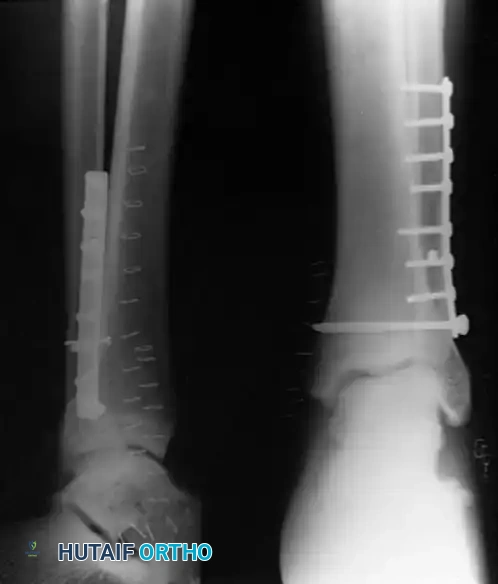

The best functional outcomes are obtained by anatomical joint restoration. While closed manipulation and casting may suffice for stable, non-displaced fracture patterns, open reduction and internal fixation (ORIF) is the gold standard for unstable injuries. For most displaced fractures, operative intervention ensures anatomical joint restoration, rigid stability, and reliable union, permitting early range of motion.

Operative Techniques for the Lateral Malleolus

When operative intervention is indicated, several techniques are available:

- Lateral Plating (Neutralization): The standard approach utilizes a direct lateral incision. The fracture is anatomically reduced with pointed reduction forceps. An interfragmentary 3.5-mm lag screw is placed perpendicular to the fracture plane, followed by a 1/3 tubular neutralization plate applied to the lateral aspect of the fibula.

- Posterior Antiglide Plating: Advocated by Ostrum for Weber B fractures, this technique involves placing the plate on the posterior aspect of the fibula. It biomechanically resists the posterior and proximal displacement of the distal fragment. It decreases the incidence of palpable hardware and avoids intraarticular screw penetration.

Surgical Indication: The AO Foundation and modern orthopedic consensus mandate open reduction and internal fixation of both malleoli for almost all displaced bimalleolar fractures to prevent post-traumatic arthrosis.

Surgical Sequence for Bimalleolar Fixation

- Lateral Side First: The fibula is typically addressed first to restore the length and rotation of the lateral column. This often indirectly reduces the talus and simplifies the medial reduction.

- Medial Side Second: Once the lateral mortise is established, the medial malleolus is directly reduced and fixed.

- Syndesmotic Evaluation: After bimalleolar fixation, the syndesmosis must be tested using the "Cotton test" (lateral traction on the fibula using a bone hook). If widening occurs, syndesmotic screws or flexible suture-button constructs are required.